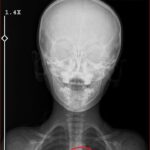

Şırnak’ta yaşayan Semra (37) ve Mehmet Ötün (40) çiftinin oğulları Aram Devran Ötün, mayıs ayında piknikteyken salatalık parçası yuttuktan sonra öksürük ve kusma şikayetleri görülünce Şırnak Devlet Hastanesi’ne götürüldü. Burada çekilen röntgen ve MR’da Aram’ın vücudunda kateter unutulduğu görüldü. Diyarbakır’daki Gazi Yaşargil Eğitim ve Araştırma Hastanesi Kadın Doğum ve Çocuk Ek Binası’na sevk edilen Aram, 5,5 saat süren riskli bir ameliyata alınarak 18 santimetre uzunluğundaki kateter çıkarıldı. Ameliyat sonrası yapılan incelemelerde kateterin kalp kapakçığına ve ciğerlerine zarar verdiği belirlendi.

Oğlunun piknikte salatalık parçası yuttuktan sonra sürekli öksürmeye ve kusmaya başladığını söyleyen Semra Ötün, “Çocuğum 3 yıl önce Steven Johnson sendromu hastalığına yakalandı. Milyonda bir görülen antibiyotikten kaynaklı bir hastalık. Doktorlar öyle söyledi. Bizi acilen Diyarbakır Dicle Üniversitesi Çocuk Hastanesi bölümüne sevk ettiler. 1 ay yoğun bakım sürecimiz oldu. 28 gün yoğun bakımda, 3 günde serviste kaldı. Damar yolundan, kasıktan serum taktılar. Kateter denilen tel çocuğun vücudunda bırakılıyor. Biz taburcu olduğumuzda fark edilmiyor. 3 yılın sonunda biz bunu fark ettik. Pikniğe gittik. Oğlum salatalık parçası yuttu ve salatalık parçasından sonra akşama kadar öksürdü. Hiçbir şekilde durmadı. Kusuyordu. Ben şüphelenmeye başladım. Çocuğum normal değildi. Sonra eşime danıştım. Akşam 21.00 civarında acile götürdük. Röntgeni ve MR’ı çekildi. Tuhaf bir şey olduğunu anladık. Doktor röntgeni gösterdi. Tel kalmıştı. Çok kötü bir şekilde. Acil doktoru film çektikten sonra bize bir tel parçasını gösterdi. Bizi bekletmeden Diyarbakır’a sevkimizi verdiler. Diyarbakır Gazi Yaşargil Eğitim ve Araştırma Hastanesi Kadın Doğum ve Çocuk Ek Binası’na gittik. Çocuğun kasıklarından anjiyo yolu ile teli çıkaracaklarını ama riskli bir ameliyat olduğunu söylediler. O süreçte çocuk gerçekten sürekli yoruluyordu. İkide bir oturuyordu. ‘Anne çok yoruldum, karnım ağrıyor’ diyordu. Ben ağrı kesiciler ile geçiştirmeye çalışıyordum. Bu telin 3 yıl boyunca çocuğumda kaldığını öğrendim. Ailece yıkıldık” diye konuştu.